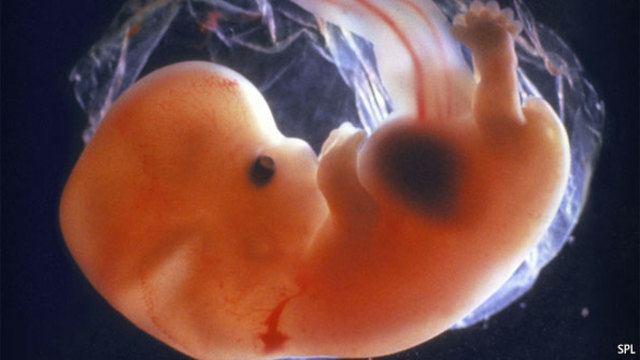

From this week until birth, the embryo is called a fetus. The fetus is about the size of a strawberry. During this week, the fetus's fingerprints will form and the mouth and nose join.

The brain is growing and producing about 250,000 nerve cells every minute. The heart and the lungs are almost completely developed, but the fetus's blood is still oxygenated through the placenta.

The baby's brain and heart are fully formed, and the baby can also feel pain. Fingernails and toenails appear.